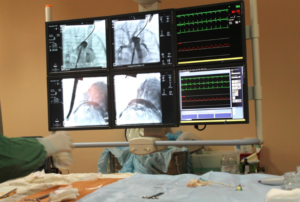

Por ejemplo en Moscú los médicos cuentan con equipos de radiografía (angiografía – Siemens 2017), un departamento estacionario, un departamento de reanimación y cuidados Intensivos, un departamento policlínico de cardiología, una sala de conferencias para impartir la teoría; todos cuentan con los más modernos equipos para el diagnóstico y tratamiento de pacientes con diversas patologías del sistema cardiovascular.

Asimismo, la sala de cirugía endovascular ofrece la posibilidad de realizar teleconferencias académico-científicas en línea.